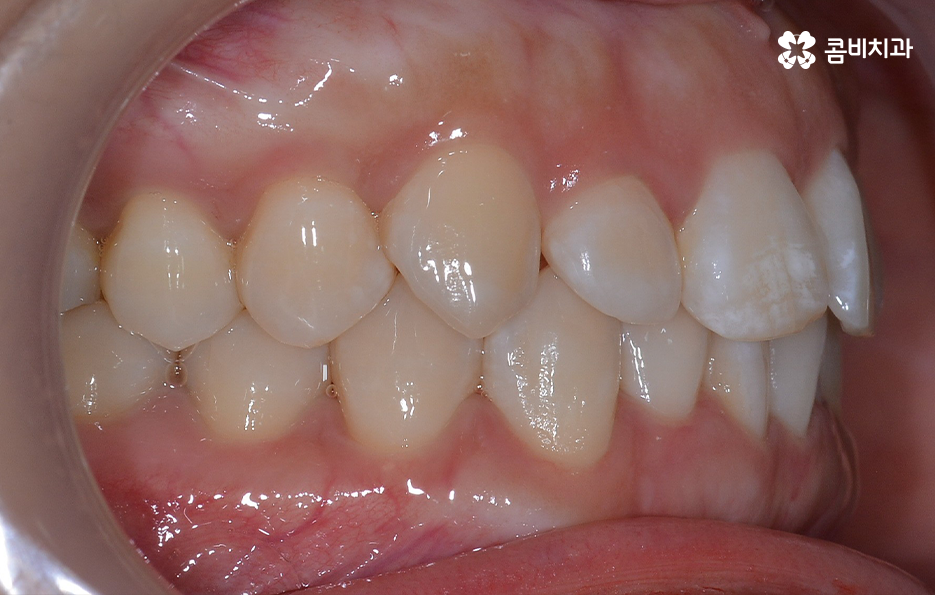

출처 아카이브 열기과거에는 주걱턱, 돌출입과 같은 부정교합이거나 덧니가 심한 경우에 치아교정을 하는 분들이 많았다면 요즘은 비교적 치열의 불규칙함이 심하지 않거나 치아가 약간 벌어진 경우에도 보다 가지런한 치열과 외모적 개선을 위해 치아교정을 알아보는 분들이 늘고 있는데요

특히 30,40대 이후에 교정하는 분들이 늘고 있는 추세인데 치아가 삐뚤빼뚤하거나 치아 사이가 벌어져서 발생할 수 있는 구강질환을 예방하는 목적과 치아가 돌출되거나 삐뚤하여 교정을 통해 외모적인 개선을 목적으로 하는 경우와 같이 다양한 목적으로 치료를 알아보실 거예요.

교정에 대해 알아보시면 단순히 치열을 가지런하게 재배열 혹은 펴는 개념만이 아니라 치아교정을 통해 부정교합을 치료하여 치아의 기능적인 부분을 개선하거나 얼굴 변화에 대한 부분, 치아의 건강 등 종합적으로 알아봐야 할 점들이 많다는 것을 알 수 있는데요.

이 중에서는 발치 여부에 대해서도 많은 고민이 되는 부분 중에 하나일 거예요. 교정 치료에서 발치를 하는 경우에는 보통 작은 어금니를 발치하여 치아의 이동 공간을 확보하는 경우가 많은데 아무래도 생니를 발치한다는 생각에 발치는 무조건 안좋다고 느끼거나 거부감을 느끼시는 분들도 많이 있어요.

교정 치료는 크게 발치와 비발치치아교정으로 나뉠 수 있는데 비발치치아교정의 경우에는 아무래도 치아가 움직이는 양도 적고 그에 따라 교정 기간도 짧은 편에 해당되고 있어요.